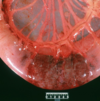

Q

This is the stomach of a horse. What lesion is shown here?

A

equine gastric ulceration